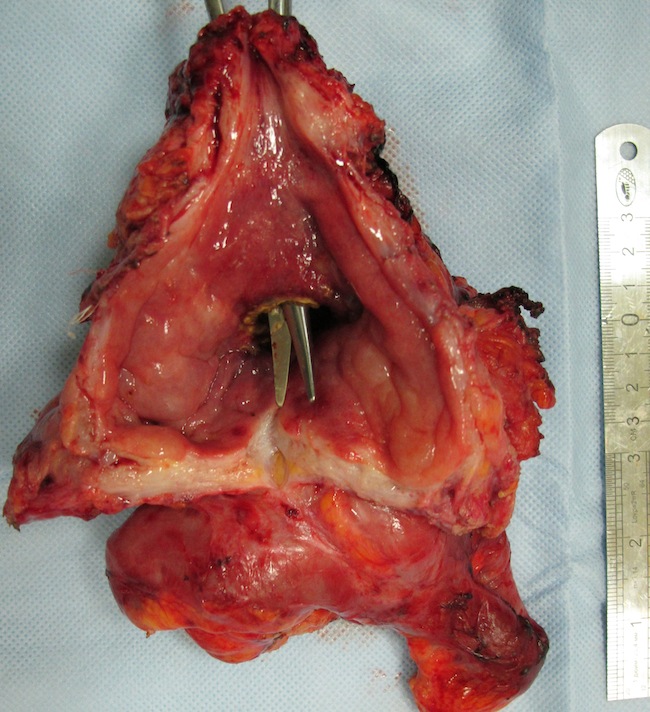

27.03.2013г. – операция: комбинированная надлеваторная эвисцерация малого таза с резекцией петли тонкой кишки: под эндотрахеальным наркозом выполнена нижняя срединная лапаротомия по старому послеоперационному рубцу. Малый таз выполнен опухолевым конгломератом, включающим культю влагалища, мочевой пузырь, прямую кишку и петли подвздошной кишки. Признаков отдаленного метастазования не выявлено.

Выполнена резекция вовлеченной в конгломерат подвздошной кишки. Мочеточники визуализированы с обеих сторон, взяты на держалки и пересечены. Мочеточники интубированы катетерами № 9 Ch. Разрез брюшины продлен до корня брыжейки поперечной ободочной кишки. Произведена диссекция клетчатки с лимфатическими узлами вдоль аорты и нижней полой вены от почечных сосудов до парааортальные лимфатические узлы, удалены. Пересечен дистальный конец двуствольной колостомы. Прямая кишка со значительными техническими сложностями мобилизована в малом тазу до диафрагмы таза. Переднебоковые связки ее пересечены. Выделена внебрюшинная часть мочевого пузыря. Пресечена уретра, передняя и задняя стенка влагалища. Уретра, влагалище ушиты Z-образными швами.

Прямая кишка на уровне нижнеампуляного отдела прошита и пересечена. Препарат, включающий влагалище, сегмент подвздошной кишки, сегмент толстой кишки, мочевой пузырь, клетчатку из области подвздошных сосудов, запирательных ямок удален. Сформирован анастомоз подвздошной кишки по типу "конец-в-конец". Контроль проходимости анастомоза. Дефект брыжейки ушит с обеих сторон. Выполнена аппендэктомия. В дистальную изолированную часть сигмовидной кишки с формированием единой площадки имплантированы мочеточники, вместе с проксимальным отделом сигмовидной кишки, выведены в левую подвздошную область.